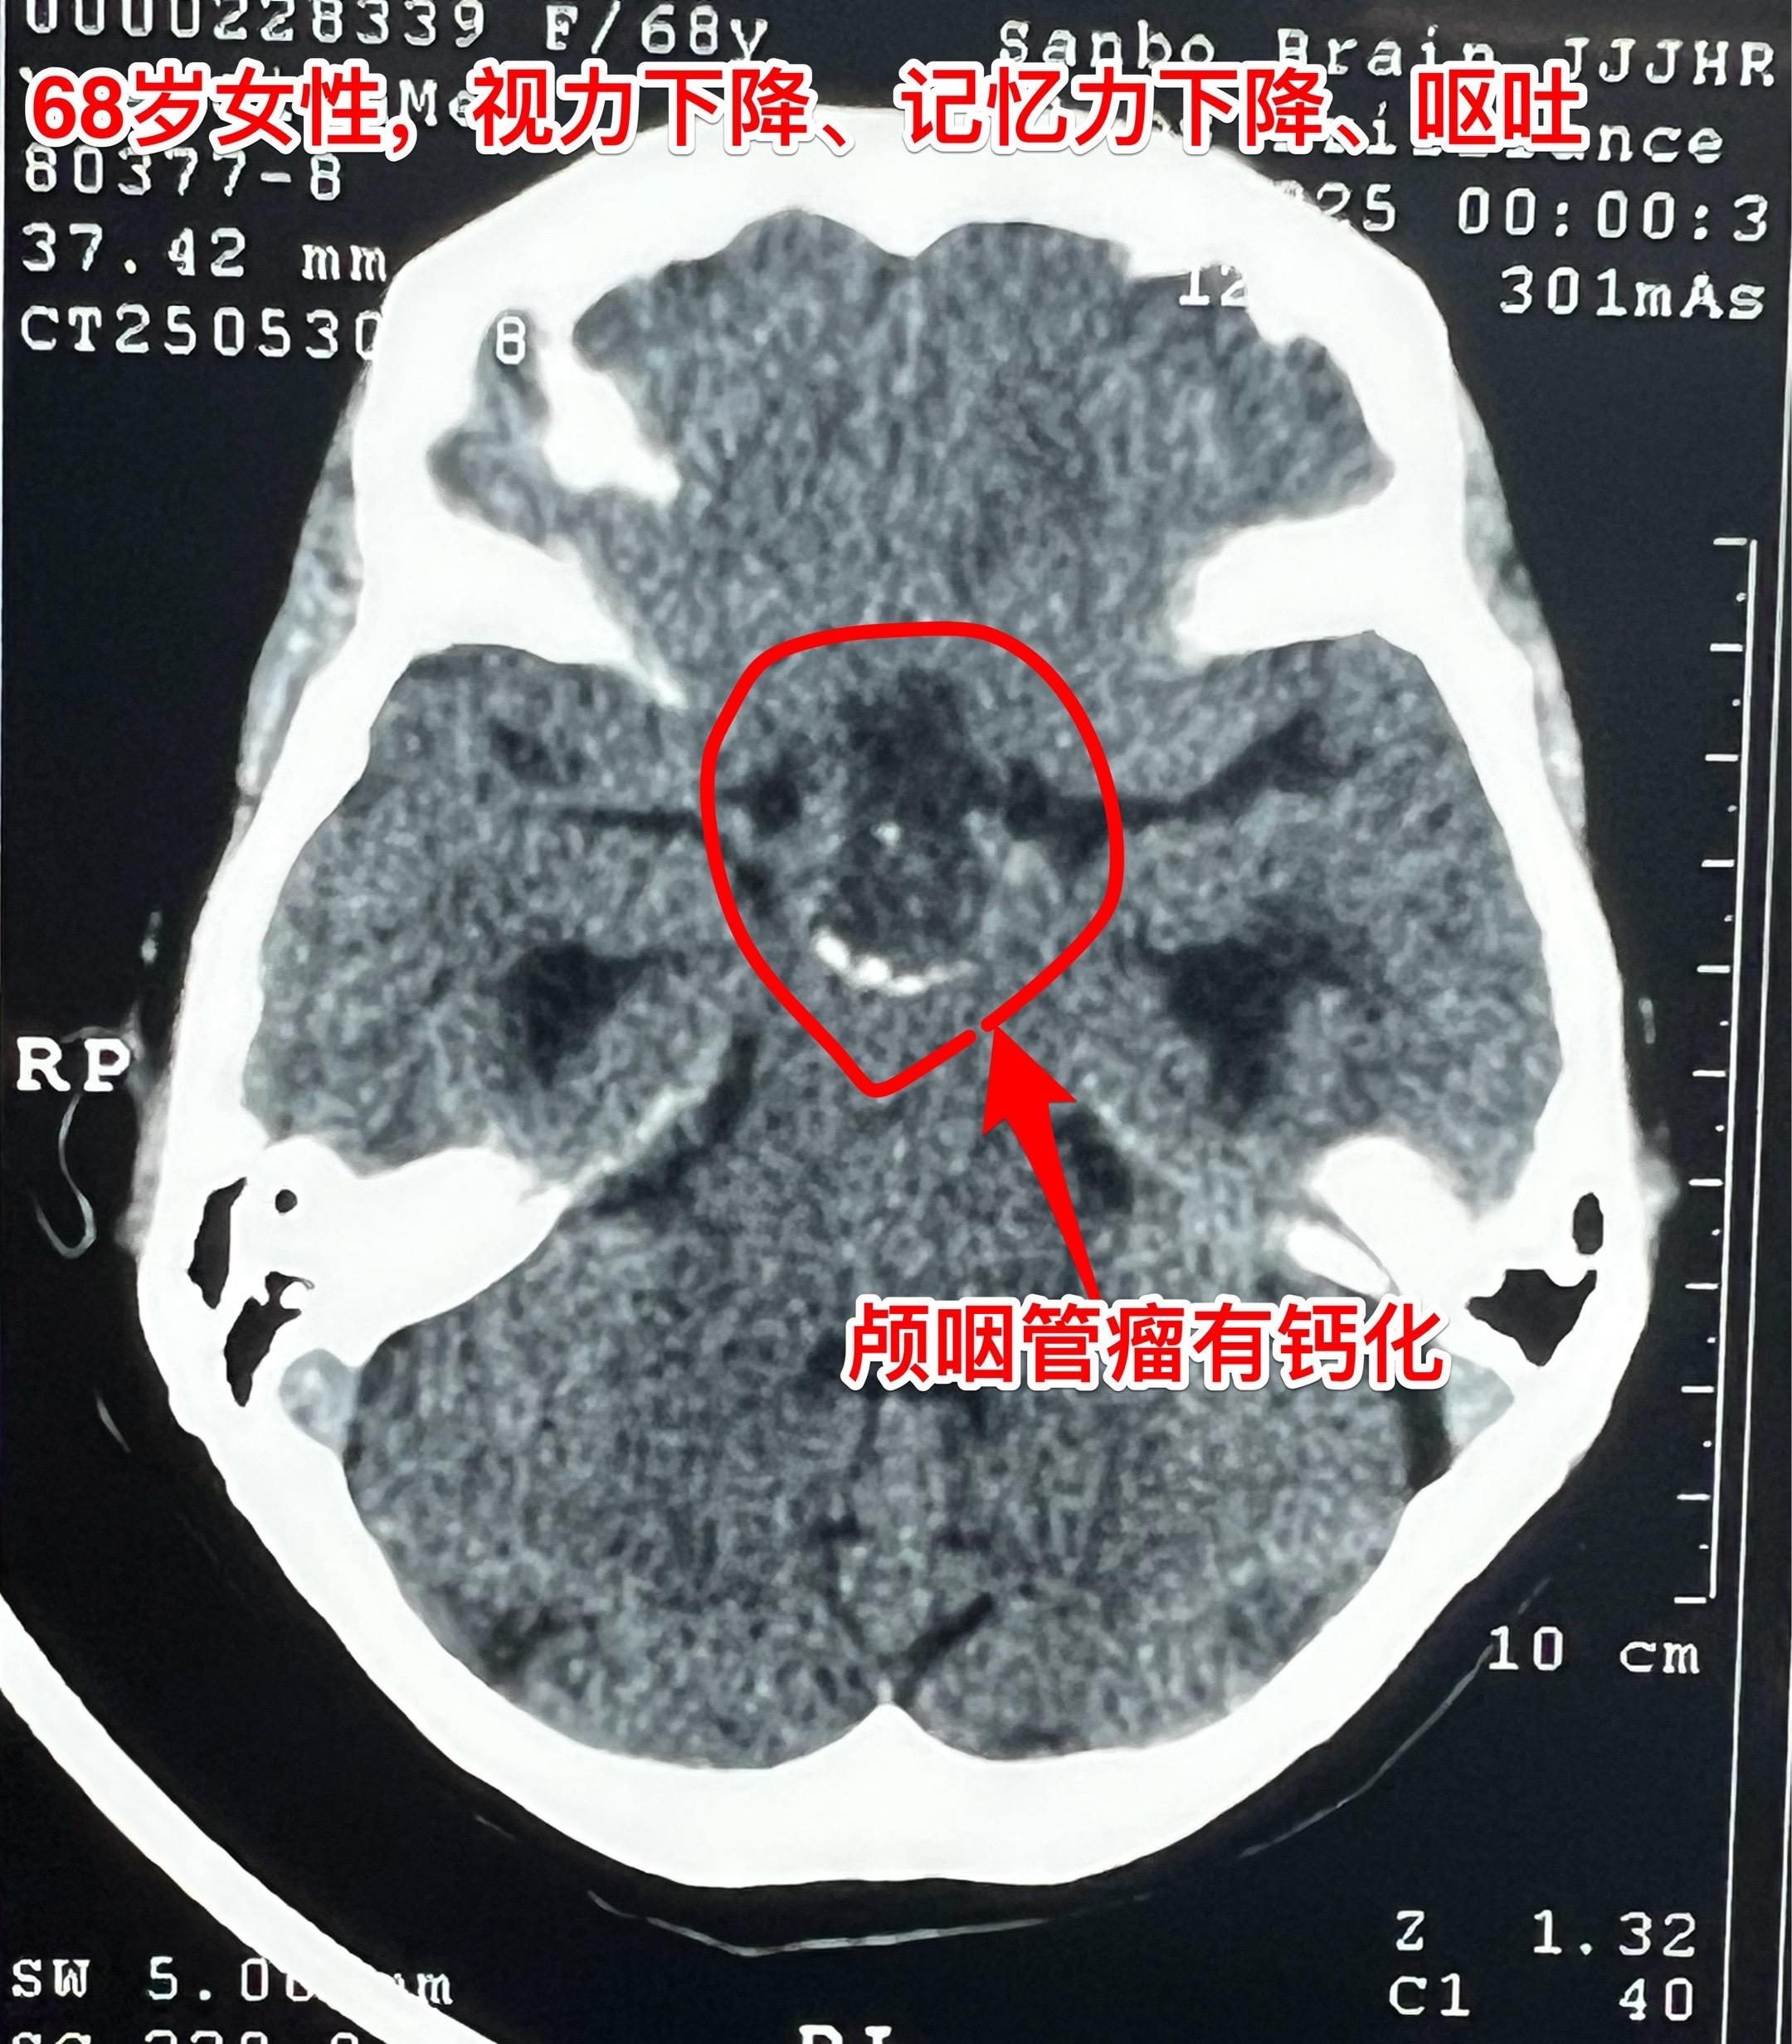

68岁老人患颅咽管瘤是否可以作手术? 颅咽管瘤并非小孩子的病,老年人也可以患颅咽管瘤。 过去十年间我科治疗过颅咽管瘤患者共计1153例次,其中53例患者年龄在60-74岁。 所以,老年人患颅咽管瘤也不是手术禁忌。 这个68岁南通市女病人因颅咽管瘤造成视力下降、头晕症状,住院前一天出现反复呕吐症状,提示颅内压升高,所以应该尽早作手术,否则会造成生命危险。2025年6月8日作了开颅手术,颅咽管瘤得到完全切除。幸运的是垂体柄受肿瘤侵蚀的不严重,得以保留。今天是手术后第